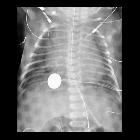

Newborn with

hypoxic ischemic encephalopathy. CXR AP shows a nasogastric tube coursing in the esophagus with its tip in the body of the stomach. The twisted wire probe coursing next to the nasogastric tube with its tip in the body of the stomach represents an esophageal temperature probe. Another twisted wire temperature probe is present in the left axilla.The diagnosis was esophageal temperature probe malfunction with the tip positioned too low in the stomach in a patient with hypoxic ischemic encephalopathy.